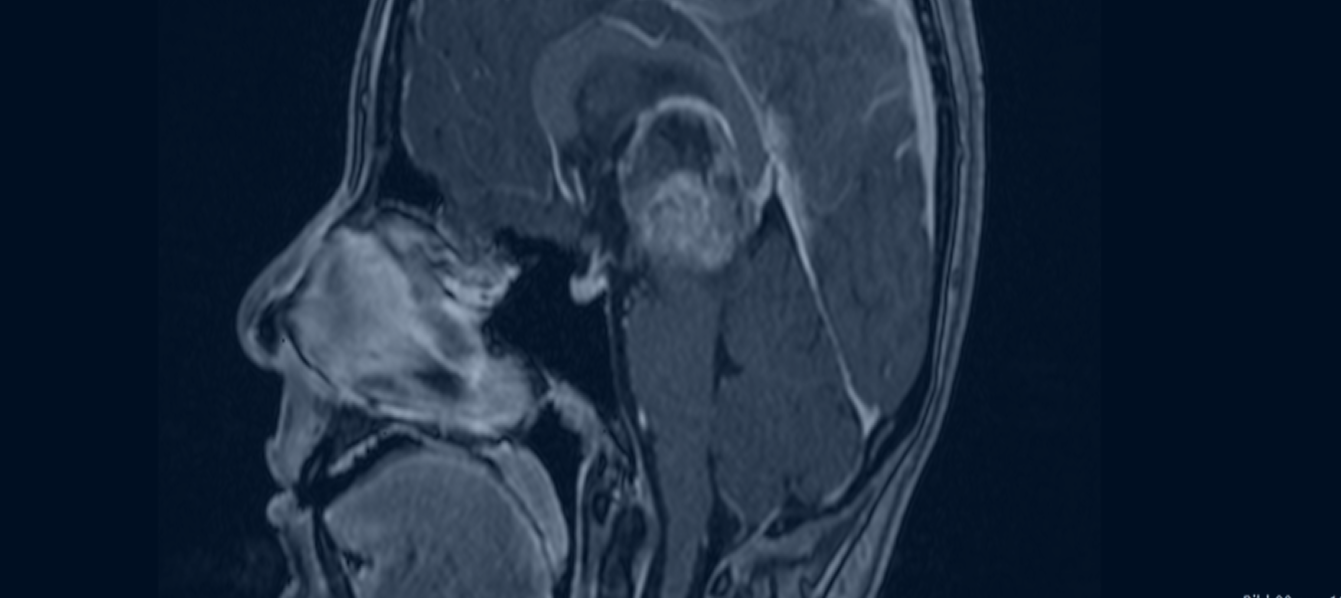

Η εικόνα 1, απεικονίζει τη ν καθοδήγηση του ενδοσκοπίου μέχρι τις κοιλίες του εγκεφάλου για να αφαιρεθεί στην συνέχεια ο όγκος ενδοσκοπικά.

Η μέθοδος εκλογής για τη χειρουργική αντιμετώπιση των ενδοκοιλιακών όγκων είναι η Ενδοσκοπική Προσέγγιση. Στην εικόνα 1 μπορούμε να αναγνωρίσουμε δυο μικρές εστίες επενδυμώματος της ΙΙΙ κοιλίας, όπως αυτές φαίνονται μέσα από το ενδοσκόπιο. Αυτή η καινοτόμος, ελάχιστα επεμβατική τεχνική διενεργείται μέσα από μια μικρή οπή (10-12 χιλιοστών (κρανιοανάτρηση).

Οι ενδοκοιλιακοί όγκοι εμφανίζονται σε όλες τις ηλικίες ενώ προκαλούν μια ποικιλία συμπτωμάτων, με κυριότερο τον υδροκέφαλο. Η χρήση του ενδοσκοπίου είναι μια εξαιρετική επιλογή που προσφέρει άριστη απεικόνιση του κοιλιακού συστήματος και τη δυνατότητα της ολικής αφαίρεσης των ενδοκοιλιακών όγκων μέσω μιας μικρής κρανιοανάρτησης/οπής. Η νευροενδοσκόπηση μπορεί να συνδυασθεί με την νευροπλοήγηση για την καλύτερη καθοδήγηση του νευροενδοσκοπίου μέχρι την περιοχή των κοιλιών στην οποία εντοπίζεται ο όγκος.